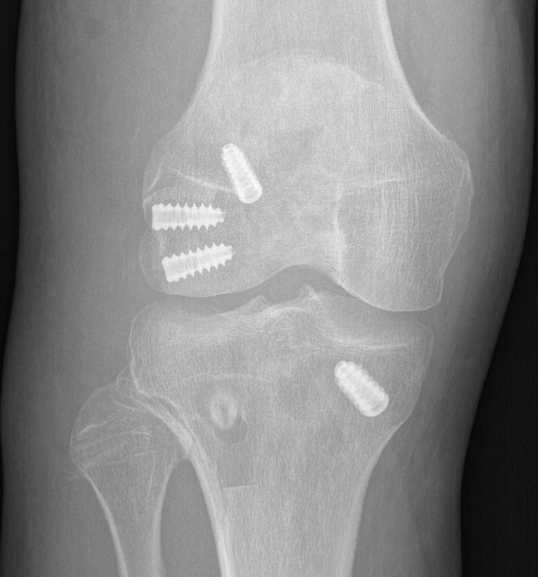

ACL + LaPrade reconstruction of LCL and popliteus